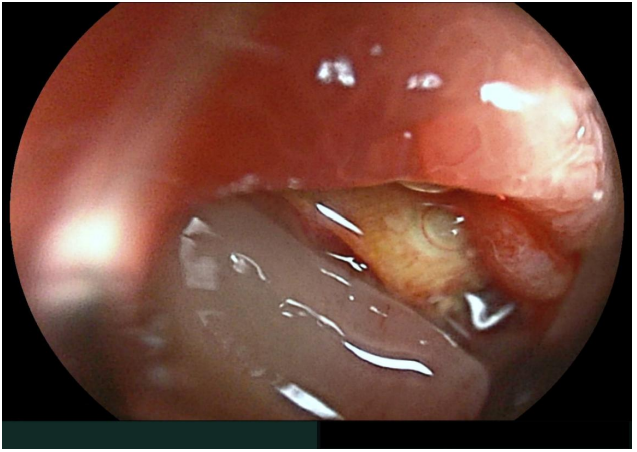

The patient was admitted with a severe IDA, confirmed by laboratory tests (Hb 4.3 g/dL, MCV 76 fl, ferritine 3 ng/ml), with no blood traces at rectal examination. Hemodynamical stability was maintained during all hospitalization; six blood transfusions was overall infused. Taking into account the previous investigations, a video capsule endoscopy (VCE) was performed showing minimal traces of red blood in the proximal small bowel lumen, without obvious mucosal lesions (Figure A). We decided to further investigate the small bowel with a per-oral device assisted enteroscopy (DAE), with identified a bulging with an adherent clot (Figure B) in the distal duodenum. The clot was gently washed with no signs of ongoing bleeding; its removal exposed a deep ulceration containing a yellowish structure behind (Figure C). An urgent angio-CT confirming the aorto-duodenal fistula (Fig. D) was performed and the patient was transferred to Vascular Surgery Department for surgical treatment.

C. Per-oral device assisted enteroscopy: deep ulceration with a yellowish mesh tubular structure (endovascular prosthesis wall) at the bottom.

Taking into account the negative bidirectional endoscopies at time of admission, a VCE was performed, showing minimal traces of red blood in the proximal small bowel lumen. This finding, without evidence of obvious mucosal lesion, might be regarded as a minor non-relevant finding. However, bleeding from AEF typically occurs in two steps: a minor initial “herald” bleeding followed by a major bleeding event. Furthermore, in the proximal small bowel, VCE can depict bleeding signs but might miss even large lesions, because of its fast progression. Therefore, when even minor stigmata of recent bleeding (i.e. fresh blood in the lumen) are observed, further investigations, like per-oral enteroscopy, are mandatory. In addition, in such a case, all the efforts to minimize mucosal trauma (to prevent false positive findings) and to maximize small bowel surface inspection (to avoid false negative examinations) should be done. Therefore, this patient underwent per-oral DAE with CO2 insufflation and with a soft hood at the tip of the endoscope. These technical tricks allowed to carefully evaluate the small bowel mucosa and to safely inspect the ulcer base and to gently mobilize the clot, identifying the prosthesis wall (the yellowish mesh tubular structure showed in Figure B).